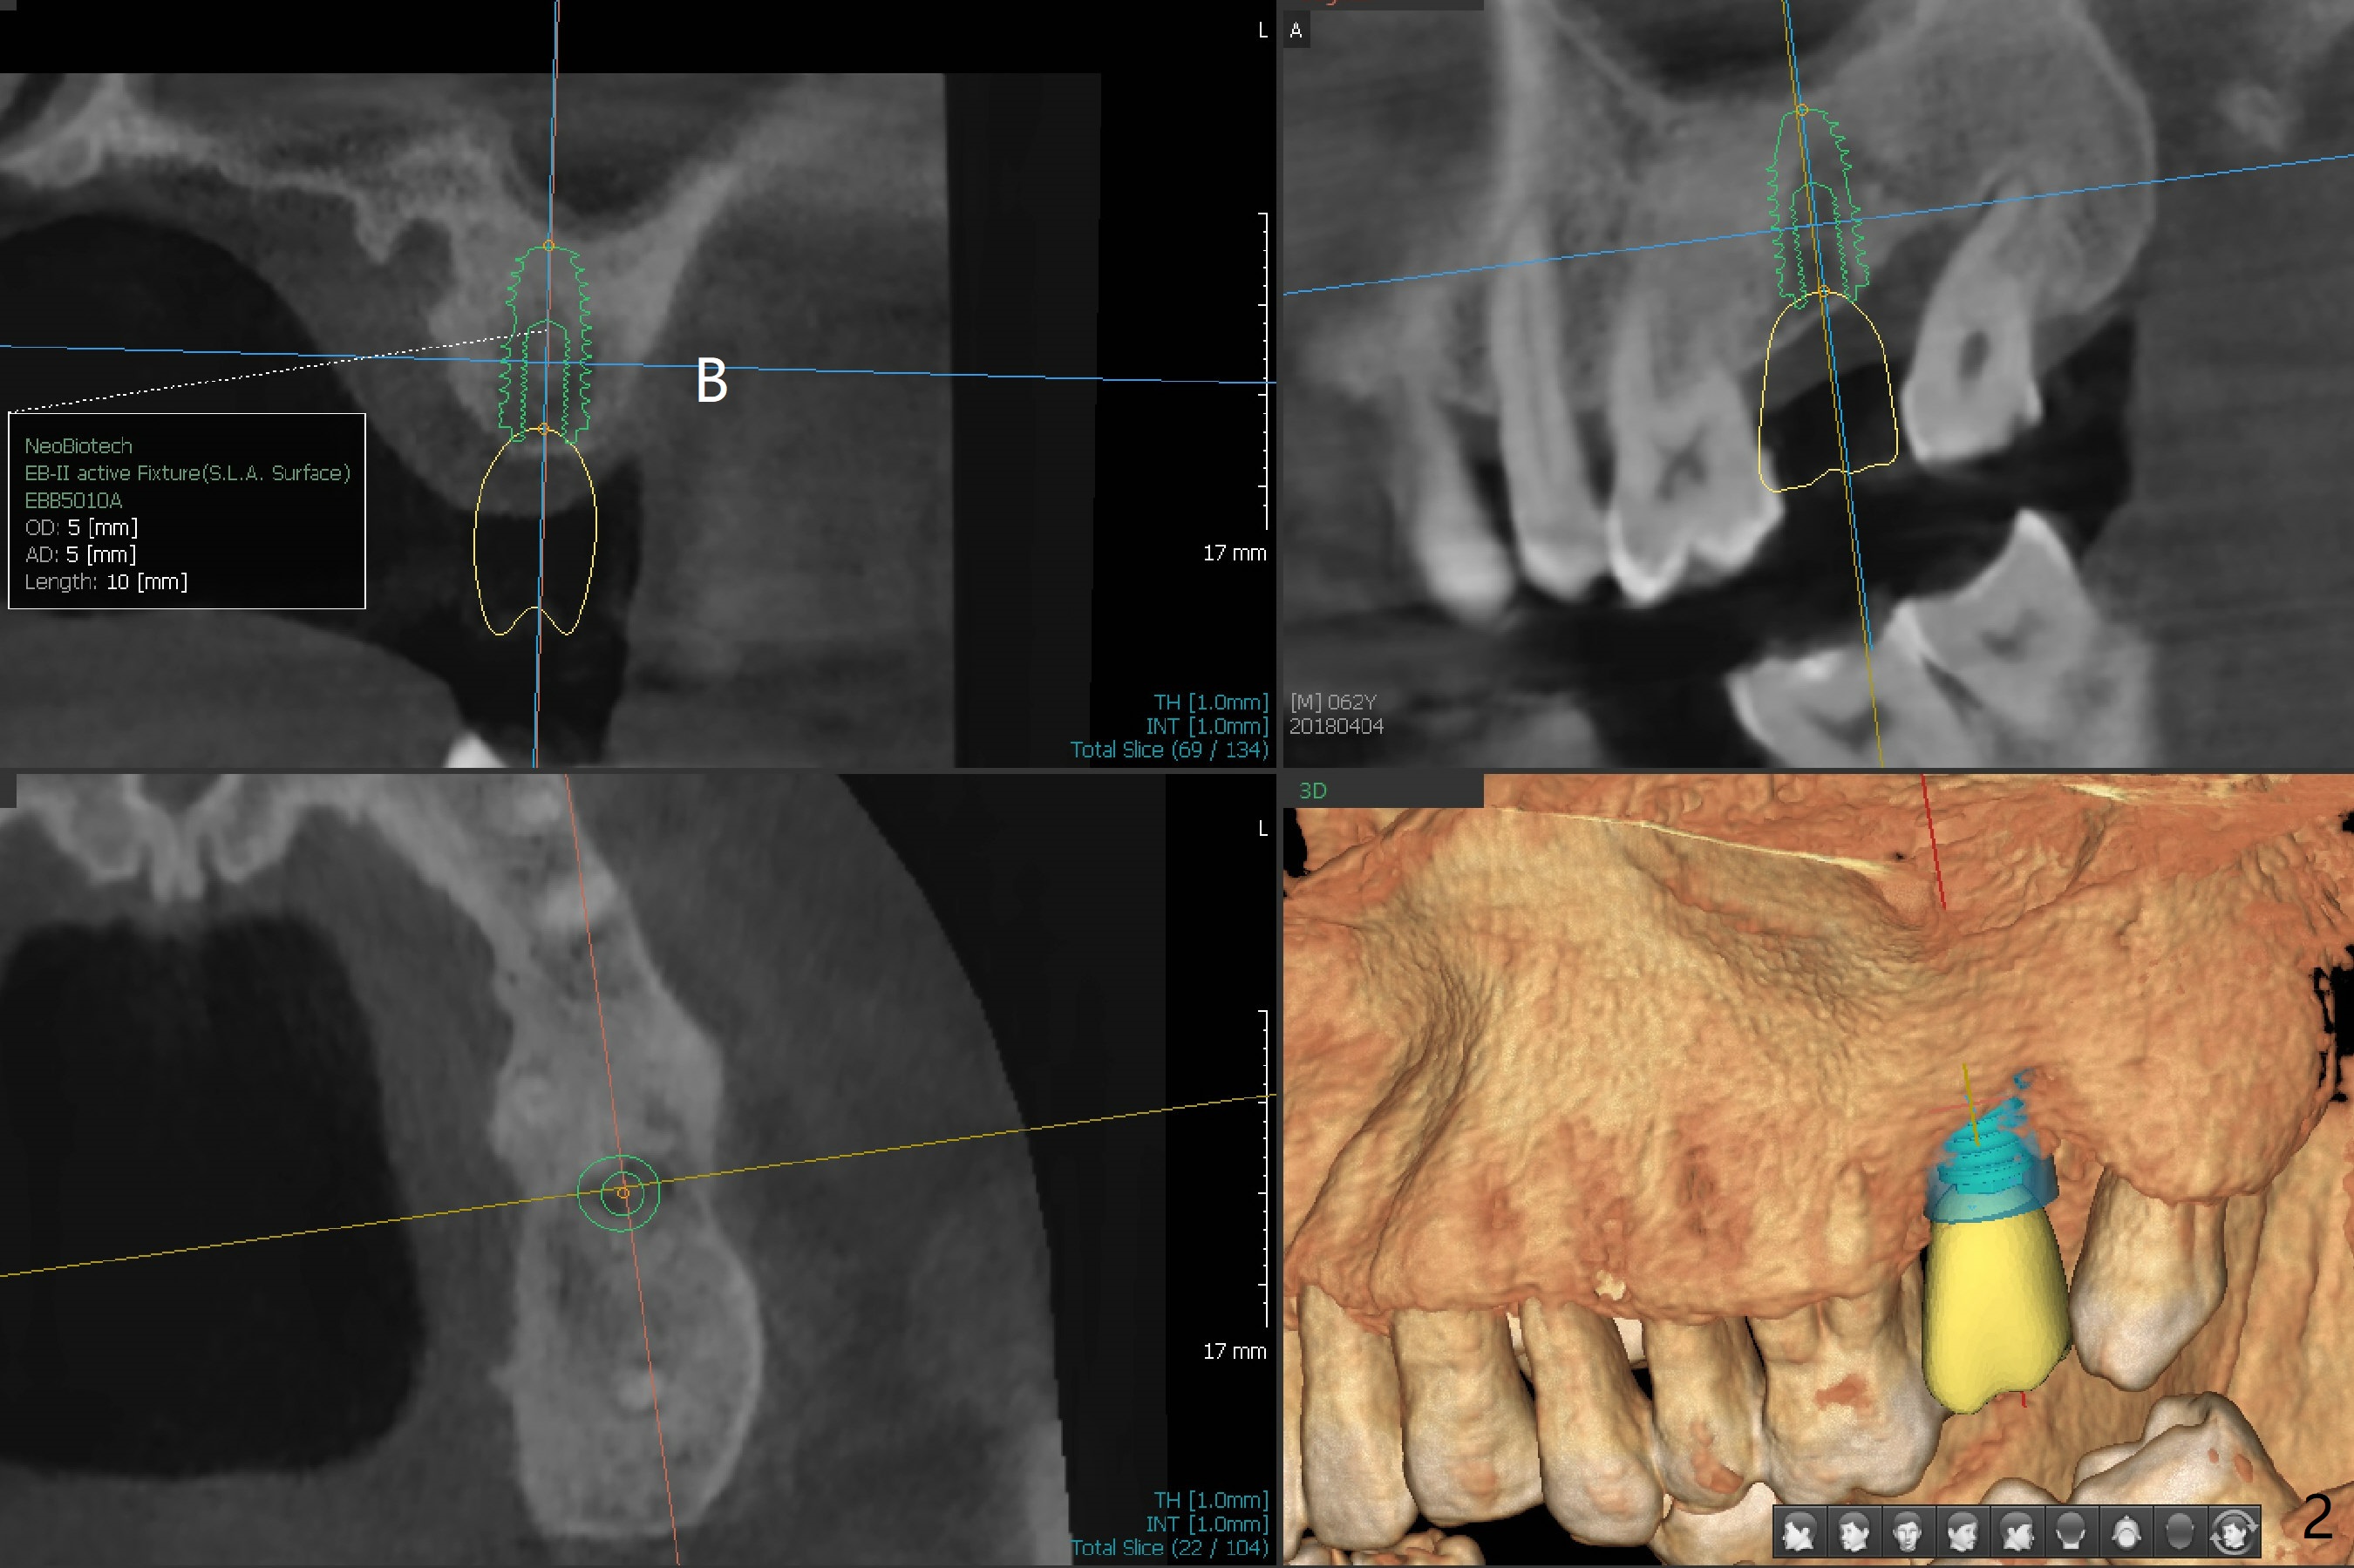

A 62-year-old man with more than 10-year-old lower RPD requests implant at #15 with history of tooth fracture (Fig.1). Guided surgery is planned at #15 (Fig.2).

The patient would like to have implants to replace the lower RPD if the 1st surgery turns out to be successful. Due to the presence of the Mental Loop (Fig.1 red dashed line) and thin bone at #29 and 30 (Fig.3,4), 1-piece implants seem to be a good option. A 2-piece implant can be placed at #19 (Fig.5). After cementation of #15 implant crown, reanalysis of CT reveals that a 3x12 mm 1-piece implant is more appropriate at #19 with a space less than a premolar (Fig.6). With 2 of narrow short implants at #29 and 30, violation of the Mental Loop is less likely to happen than a single one in the middle of the edentulous area (Fig.7).